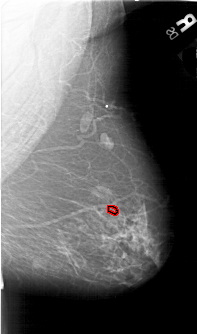

A_1646_1.LEFT_CC

LEFT_CC LINES 6376 PIXELS_PER_LINE 3856 BITS_PER_PIXEL 12 RESOLUTION 43.5 NON_OVERLAY

FILE: A_1646_1.RIGHT_CC.OVERLAY

TOTAL_ABNORMALITIES 1

ABNORMALITY 1

LESION_TYPE CALCIFICATION TYPE PLEOMORPHIC DISTRIBUTION CLUSTERED

ASSESSMENT 3

SUBTLETY 2

PATHOLOGY BENIGN